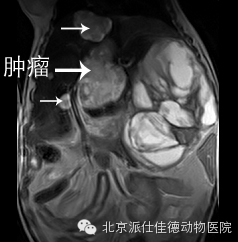

14.有些动物突然出现贫血,也没有发生外伤,腹围突然增大,经检查发现内脏大出血,最常见的是血管瘤破裂,如脾脏肿瘤破溃、肝脏肿瘤破溃、主动脉夹层瘤破裂等等。